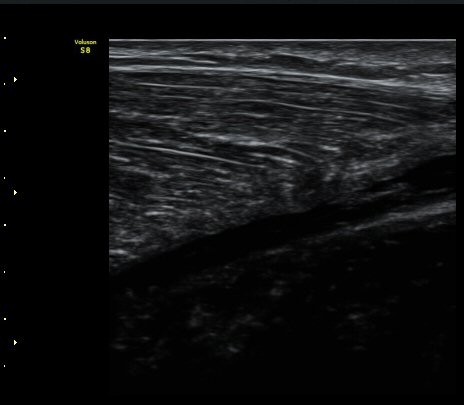

ºñº¹±Ù Ⱦ´Ü¸é°Ë»ç¿¡¼­ ºñº¹±Ù ³»Ãø, °¡Àڹٰ̱ú Á¢ÇÕ ºÎÀ§ÀÇ ÆÄ¿­°ú ¼ö¾× Àú·ù°¡ °üÂûµÊ(±×¸² 4)